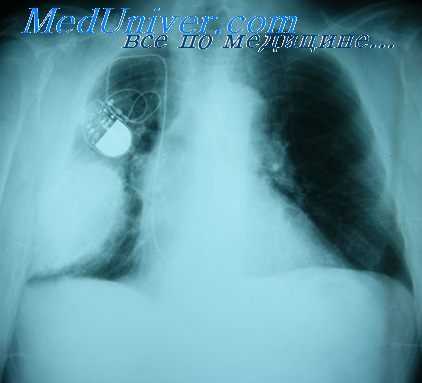

- Рентген. Полипозиционная рентгенография и рентгеноскопия легких при эмпиеме плевры обнаруживают интенсивное затенение. Для уточнения размеров, формы осумкованной эмпиемы плевры, наличия свищей выполняют плеврографию с введением водорастворимого контраста в плевральную полость. Для исключения деструктивных процессов в легких показано проведение КТ, МРТ легких.